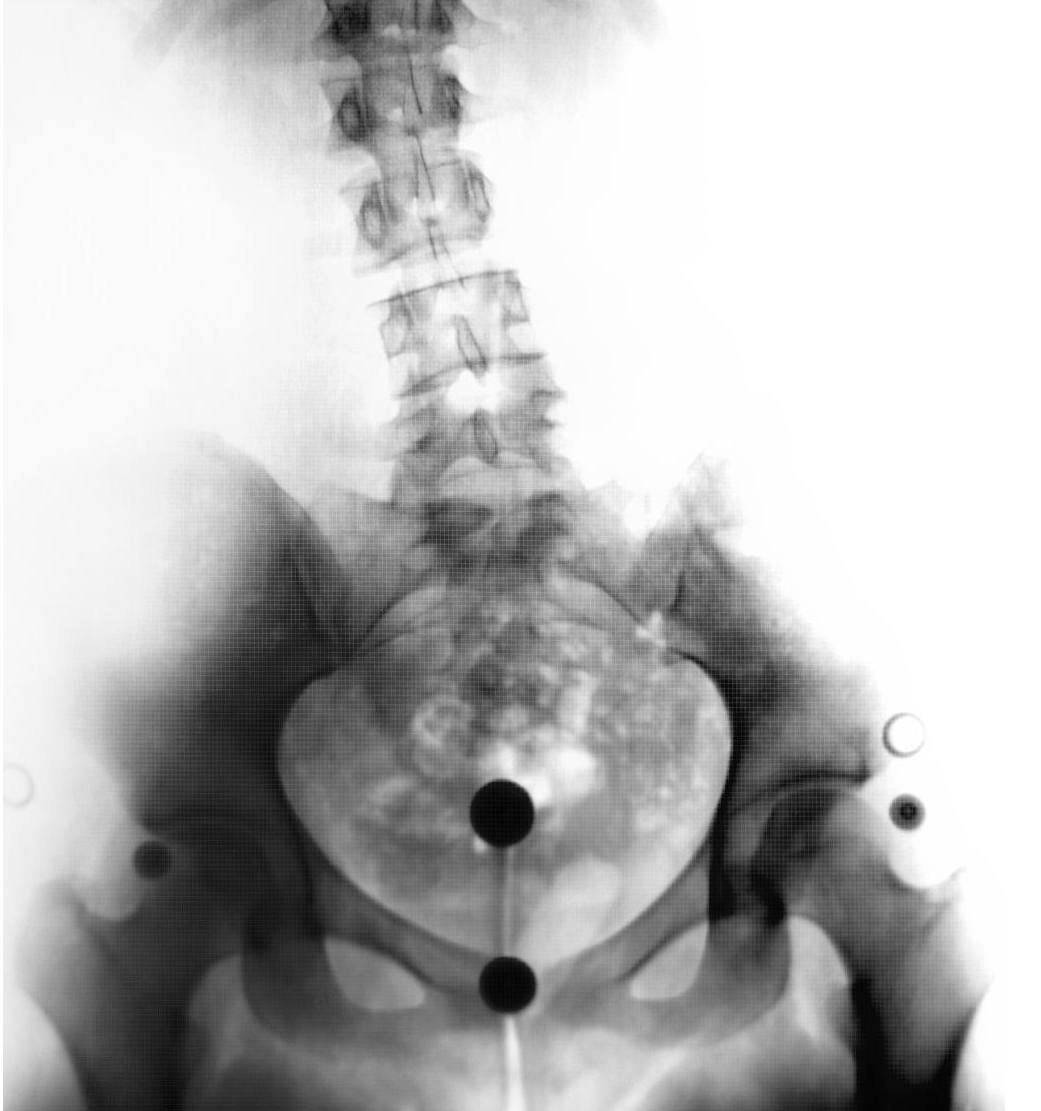

With a back procedure off the table, he presented a different proposal. Something else had been detected during the MRI he’d ordered: a tear in the cartilage of my left hip, as well as an impingement. News of a tear wasn’t shocking, my hip had been clicking for ages and I’d had some degree of pain in the joint for my entire adult life, though nowhere close to the pain I felt in my back. The specialist believed that an arthroscopic hip surgery to fix the tear could even out my gait, and that this change in my gait would most likely take some of the strain off my spine and relieve some of the constant pressure I felt in my lower back. It could make the spasms stop and help with the sciatica. It almost seemed easy.

My second opinion led me to a different surgeon, who, after taking all new images and doing a full examination of my weak and scarred body, informed me I’d need another surgery to repair the harm done during my recovery from the first one. I’d developed severe tendonitis in my iliopsoas muscle that would need to be released surgically. New impingements had formed and caused new tears in the cartilage. Small fragments of bone and cartilage had broken off due to the impingements, and would need to be removed. My bursitis had returned with vengeance, and I was now showing signs of early arthritis. Had these injuries been caught early enough, I wouldn’t have needed more interventions than good physical therapy and maybe some steroid injections to deal with the inflammation, he explained. But they hadn’t been caught. Not by anyone but me.

In a few days, I will undergo my fourth arthroscopic hip surgery. This time the work will be done on my right hip, which has taken all my weight since my first surgery on the left side. I no longer think to ask when I’ll be able to golf again; instead my questions are about being able to stand, and how I’ll carry and chase my daughter, now an incredibly active four-year old. My body barely resembles the one that sat in Dr. X’s office all those years ago. Muscles have atrophied, weight has been gained, and even my skin appears to lay differently on my legs, which haven’t run or jumped or skipped in so long they may not remember how. I have one long scar running down my left outer thigh where my IT band was harvested during my third surgery, and eight portal holes mapping a constellation on my hip. My husband and I rarely eat in restaurants, the chairs are too uncomfortable, and we only see movies in theaters with recliners. I never put on my shoes without discomfort, and I no longer own a single pair of heels. Every move I make is calculated, each step has a consequence.